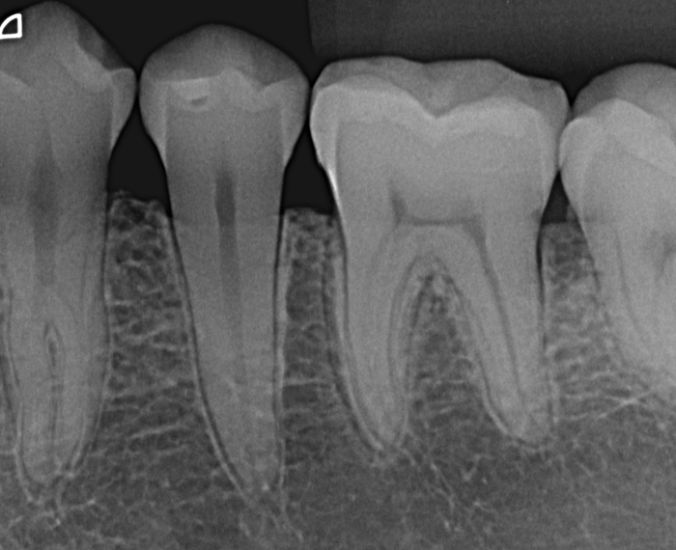

Radiografia periapical

Radiografia periapical de diagnóstico.